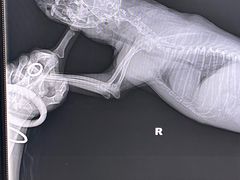

• 北京赛佳动物医院

• -北京赛佳动物医院

吉祥兔 | 24-03-01